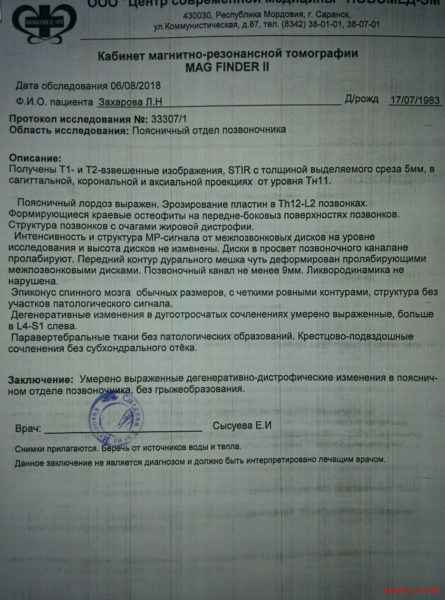

МРТ головного мозга: Расшифровка снимков и Интерпретация

Раздел: Визуальные уроки